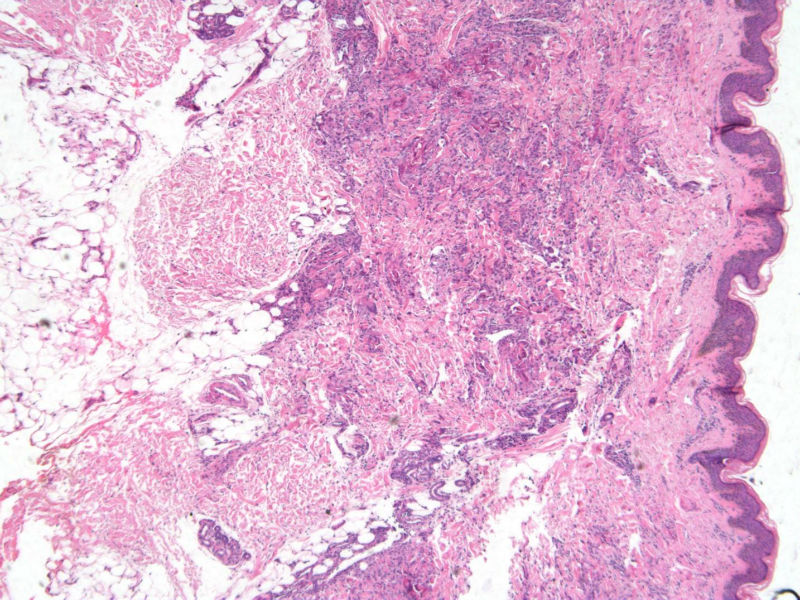

患者 男,8岁,双小腿渐粗红肿伴痒20余天,皮疹渐扩大,且出现硬化萎缩,入院后发现肺吸虫(+)。临床考虑:肺吸虫病硬皮病。请问斑竹大人考虑啥?

• 双小腿红肿伴痒20余天图2

图2

肺吸虫引起的嗜酸性粒细胞增多性疾病

肉芽肿性病变。肺吸虫能继发硬皮病吗?

肉芽肿中央不是凝固性坏死,好像是胶原纤维,否为环状肉芽肿或类脂质渐进性坏死

要考虑Wells综合征,依据有肺吸虫检查阳性、皮疹表现为肉芽肿样表现,可见到火焰征,不知道临床上血液分析检查结果如何,以及其他的检查结果怎么样?

肺吸虫皮下结节表现为肉芽肿炎症,这里的图片所显示的就是真皮及皮下组织的肉芽肿炎症,若是肺吸虫所致,按理是多少能见到嗜酸粒细胞的,但这里确实是没有看到,也没见可以的虫体征象,是没切到?也似乎没见很明显的硬皮病相关表现。

但是结合病史,患儿的皮肤改变可能还是用跟肺吸虫有关的东西来解释为妥?

补充(临床医生邮件提供)该病人是一个8岁的小男孩,此次就诊主因双小腿肿胀发硬伴痒20天入院。既往体健,无内脏疾病史,入院时无发热、咳嗽、咳痰,无腹痛、腹泻等不适。专科检查:双小腿弥漫肿胀性褐色斑块,皮疹边界清楚,左小腿较右小腿肿胀明显,左小腿皮肤弹性较正常差,皮温正常,皮肤表面未见抓痕,未见红斑、丘疹、结节等,未见糜烂、破溃。入院查血分析嗜酸性粒细胞百分之六十多,余未见明显异常;体液免疫是IgE升高明显,有一百多倍吧,具体记不清。行肺吸虫皮试阳性,胸部CT及全腹CT检查均可见感染性病变,颅脑CT未见异常。给予杀虫治疗1疗程后,左小腿肿胀明显消退,现两小腿粗细相当,左小腿肿胀发硬也明显缓解,但褐色色沉一直未见明显消退,而且还向大腿蔓延,未见明显肿胀发硬的改变。患者现无瘙痒、肿胀感等不适。患者皮疹并不是肺吸虫病的典型皮疹,故行病理检查明确皮疹是否于肺吸虫病相关。

1、患者的皮损与血液中嗜酸性粒细胞增多有关,病理改变的确类似Wells综合征的灶状坏死,但没有特异性。

2、嗜酸性粒细胞增多可以表现为毛囊炎,蜂窝织炎,脂膜炎,筋膜炎,嗜酸性皮病和增多综合征等,

3、其产生的原因常常是寄生虫,此例明确有肺吸虫。所以两者有明确的相关性。